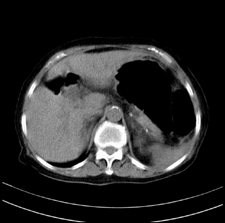

患者,女,75岁。腹痛,体黄5日,膝胸位时腹痛缓解。肝功能明日出来。彩超提示胆总管占位,未见血流信号。心电图提示s-t段改变。患者体质较弱,未能增强。

胆总管多发结石伴肝内外胆管轻度扩张。

胆总管上段,腔内有软组织密度影 ,ct值36-44hu。大家看有没有胆管癌的可能。

典型胆总管多发结石;增强扫描前后ct值是否发生改变是鉴别结石与占位的依据。